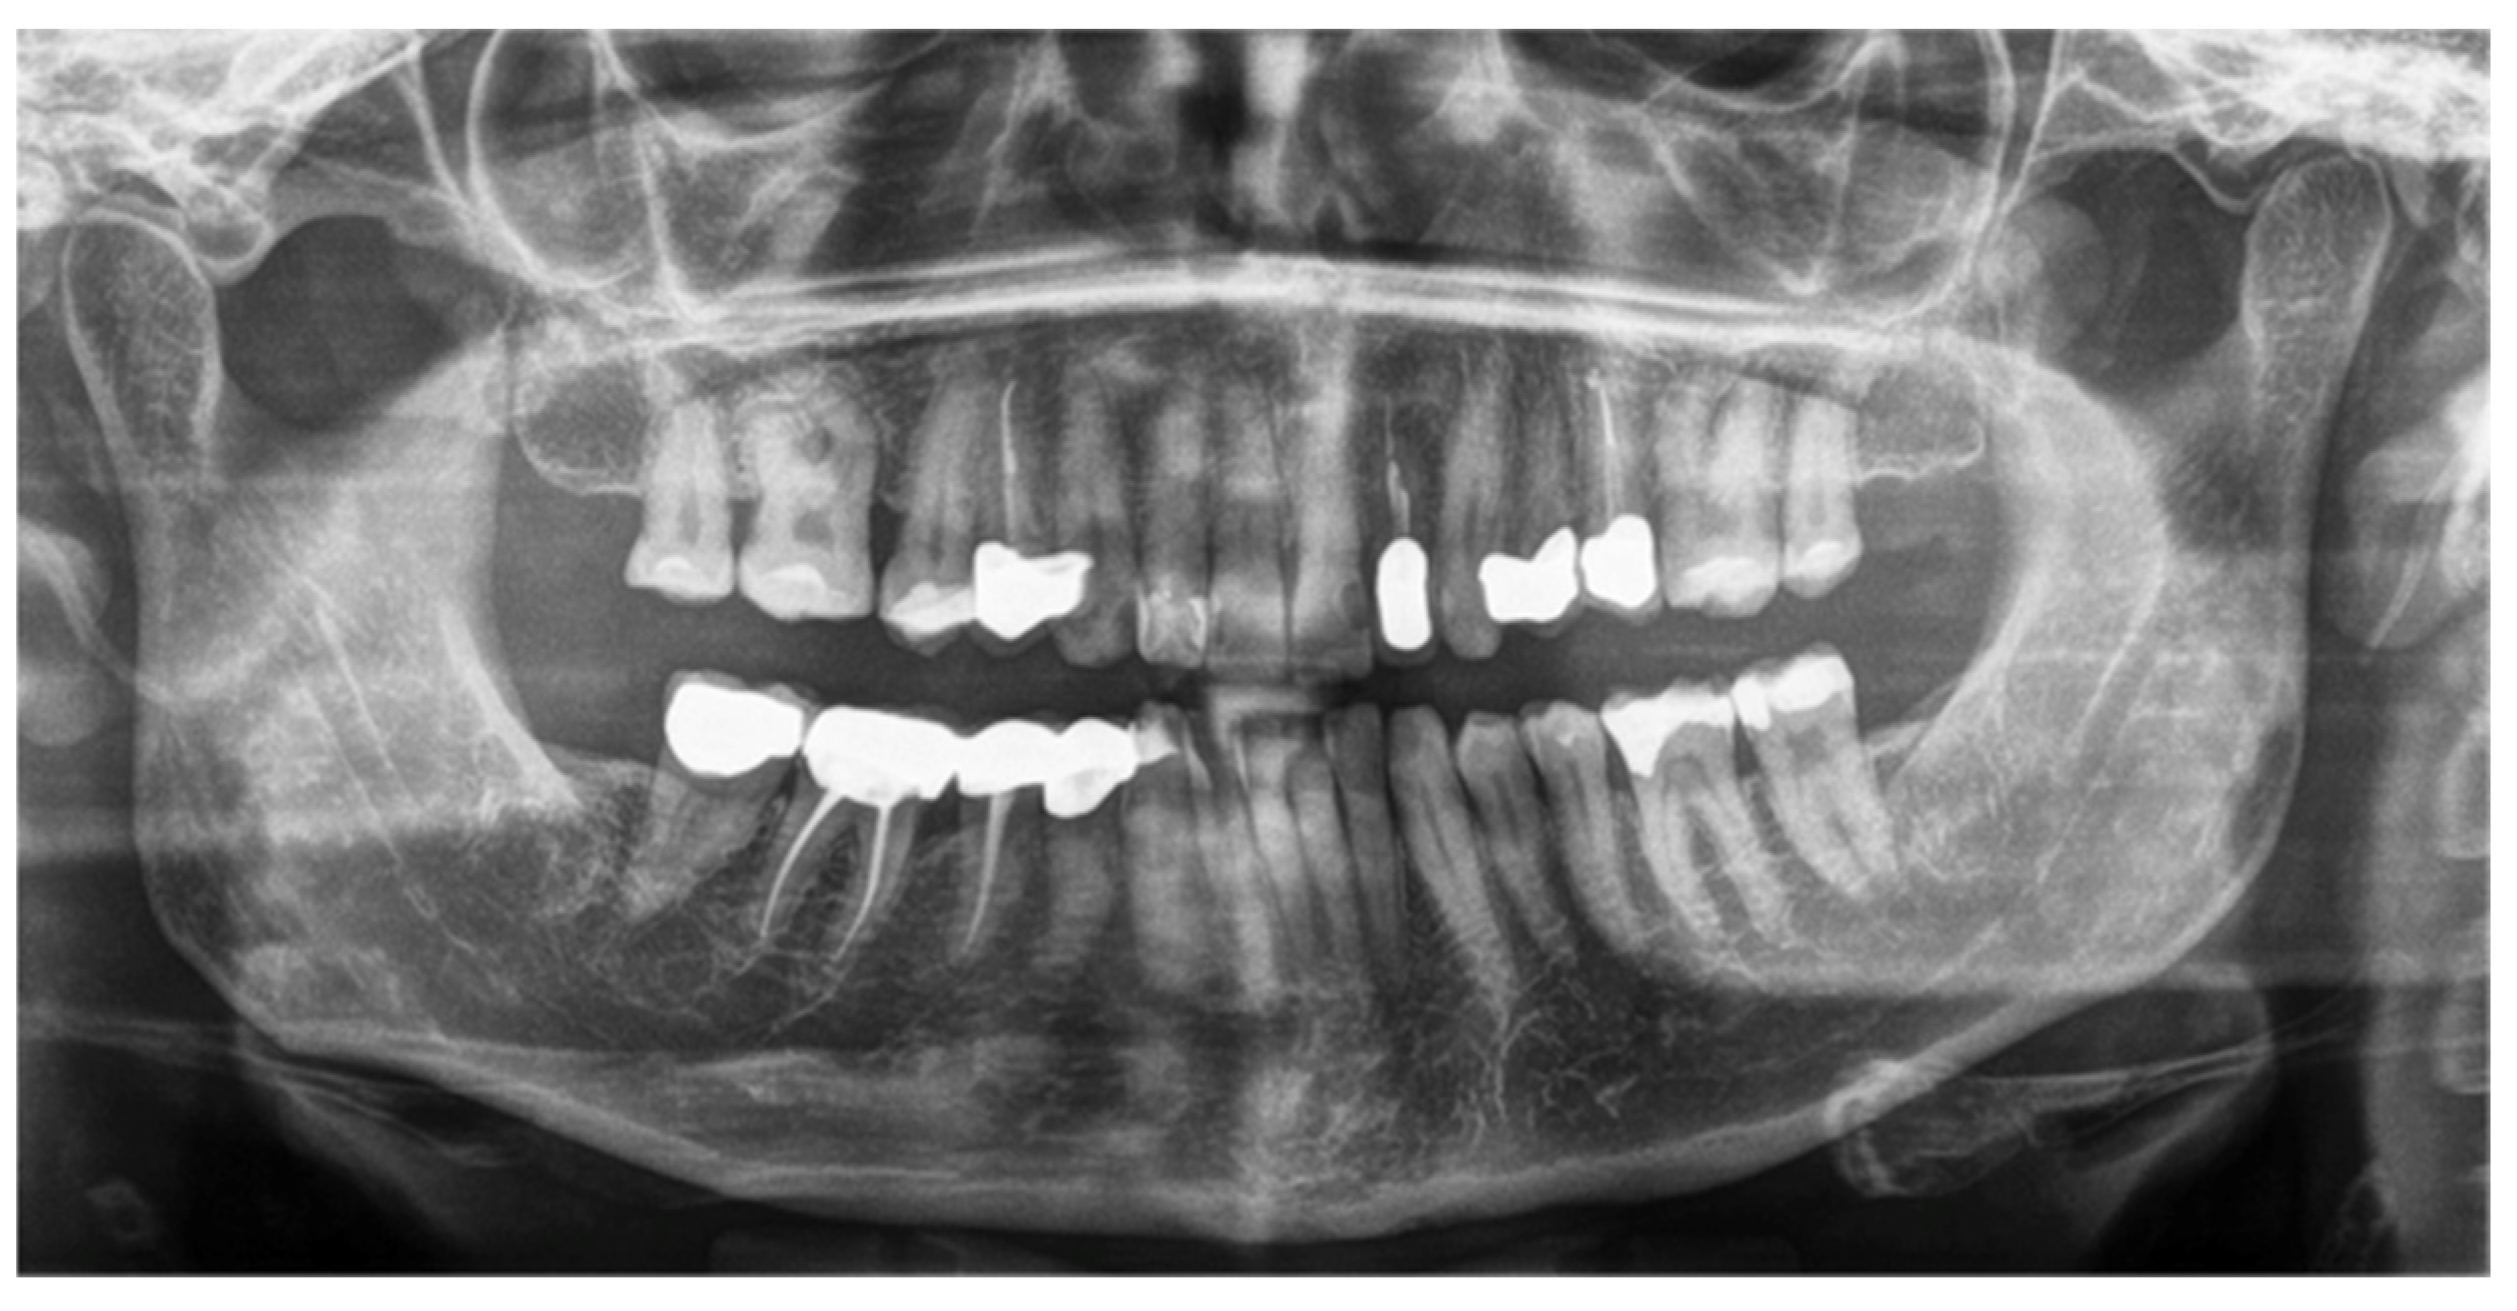

The panoramic radiograph showed a focal sclerosis of the alveolar bone surrounding the first right molar and a thickening of the lamina dura (Figure 2).

Figure 2. The panoramic radiograph was significant for aspecific signs: mild bone trabecular thickening around the first right molar roots without apical rarefaction or periodontal marginal bone reabsorption.